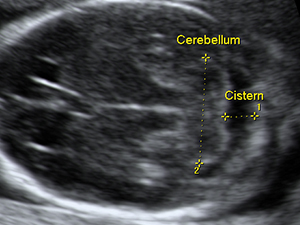

懷孕17週的胎兒小腦